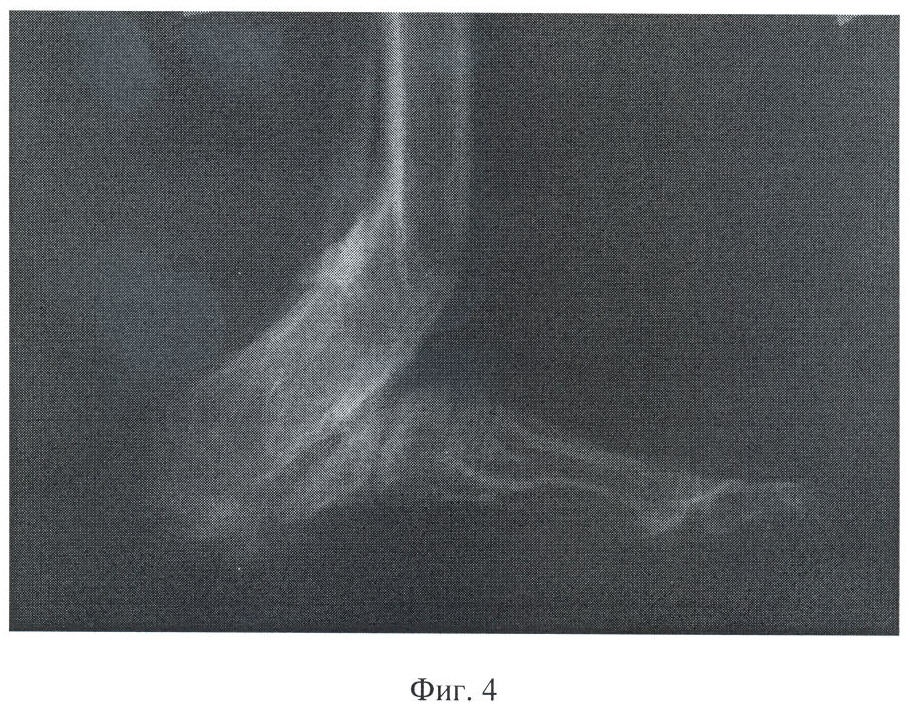

Фиг.4 – рентгенограмма левой стопы больного К. после лечения.

После придания заднему отделу стопы анатомически правильных контуров и необходимого размера аппарат перевели в режим стабильной фиксации, которую поддерживали в течение 110 дней. При этом в результате поддержания контакта зоны регенерата, сформированного при развороте блока фрагментов таранной и большеберцовой костей с кубовидной костью, получен кубовидно-берцовый синостоз.

После демонтажа аппарата дополнительной иммобилизации конечности не производили; больной прошел курс ЛФК.

В результате лечения, общая продолжительность которого составила 263 дня, полностью купирован остеомиелитический процесс, восстановлена опороспособность и максимально приближенная к естественной форма заднего отдела стопы. Больной ходит с тростью, полностью нагружая оперированную конечность. Пользуется обычной обувью. На контрольном осмотре через 5 лет достигнутый результат сохраняется, больной жалоб не предъявляет, свищей, ран нет, движения в тазобедренном и коленном суставе в пределах нормы, длина конечностей одинаковая.